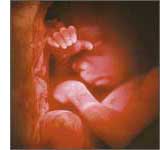

Вік плоду - 19 тижнів (Вагітність - 21 тиждень)